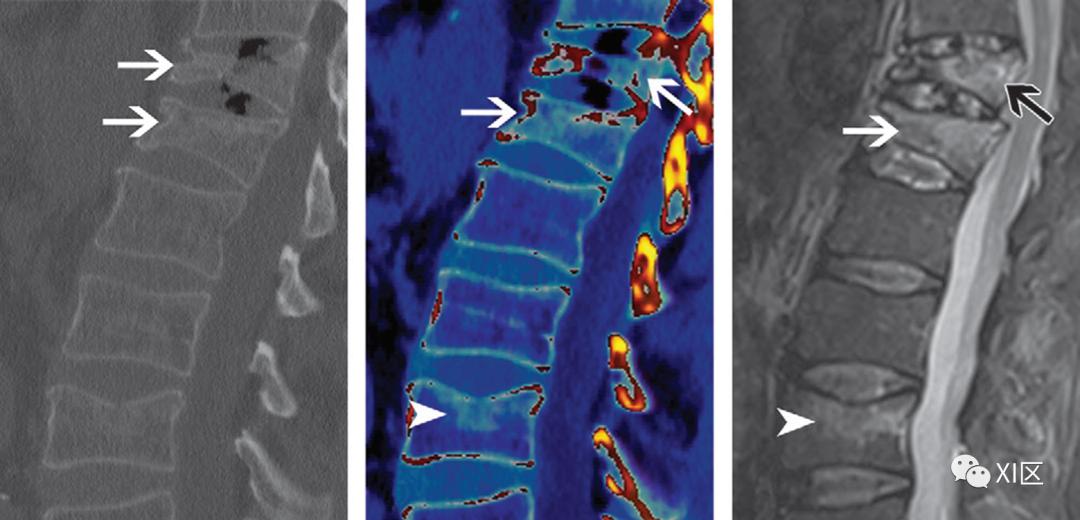

双能CT扫描产生的水肿图像有助于检测急性缺血性脑卒中。

对于急性缺血性脑卒中的诊断和治疗,灰质水肿的检测至关重要;据报道,双能量CT扫描生成的水肿图非常有用。“X-map”是一种在平扫双能CT扫描中识别急性缺血性病变的应用,它使用三种物质分解创建了一个虚拟的灰质和水含量图。X-map上的病变清楚地反映了急性缺血性脑卒中引起的脑水肿的含水量。X-map和扩散加权图像上的结果之间有很好的相关性。该方法将有助于急性缺血性卒中患者早期制定治疗策略。

图19 急性缺血性脑卒中。(A-C)发病后3小时2分钟获得的混合、低千伏和高千伏图像显示左额叶出现早期症状(箭头)。在检测急性缺血性病变时,混合等同于高千伏,低千伏低于混合和高千伏。(D)发病后3小时2分钟获得的X-Map显示,与标准CT相比,左额叶的明确异常(箭头所示)。(E)发病3.5小时后获得的扩散加权MRI显示左额叶异常信号(箭头)。肝脂肪分数与肝纤维化评估